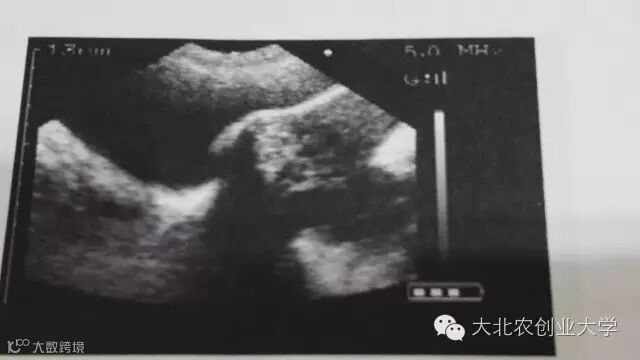

B超

操作方法:

1、使母猪保持站立姿态,扫描仪探头涂上凝胶并置于腹股沟处;

2、确保手臂、手、膝盖和脚趾不要挤压仪器;

3、缓慢移动探头知道发现清楚的胎儿图像;

4、只有发现至少2个清楚的胚泡时,才能确定怀孕,如果找不到胚泡就扫描另一侧。

优点:

1、快捷(30秒);

2、从妊娠期24天起非常可靠;

3、99%的准确率;

4、有效缩短非生产天数。

缺点:

1、仪器昂贵;

2、缺乏经验的操作者容易漏掉很多空怀或者将妊娠猪误诊为空怀。

总结:

1、常见的误诊来源是将黑点误认为胎囊,或将子宫内液体形成的小黑点误认为早期妊娠;

2、检测时间:配种后24天,38天。

B超检测图片讲解

妊娠24天图像